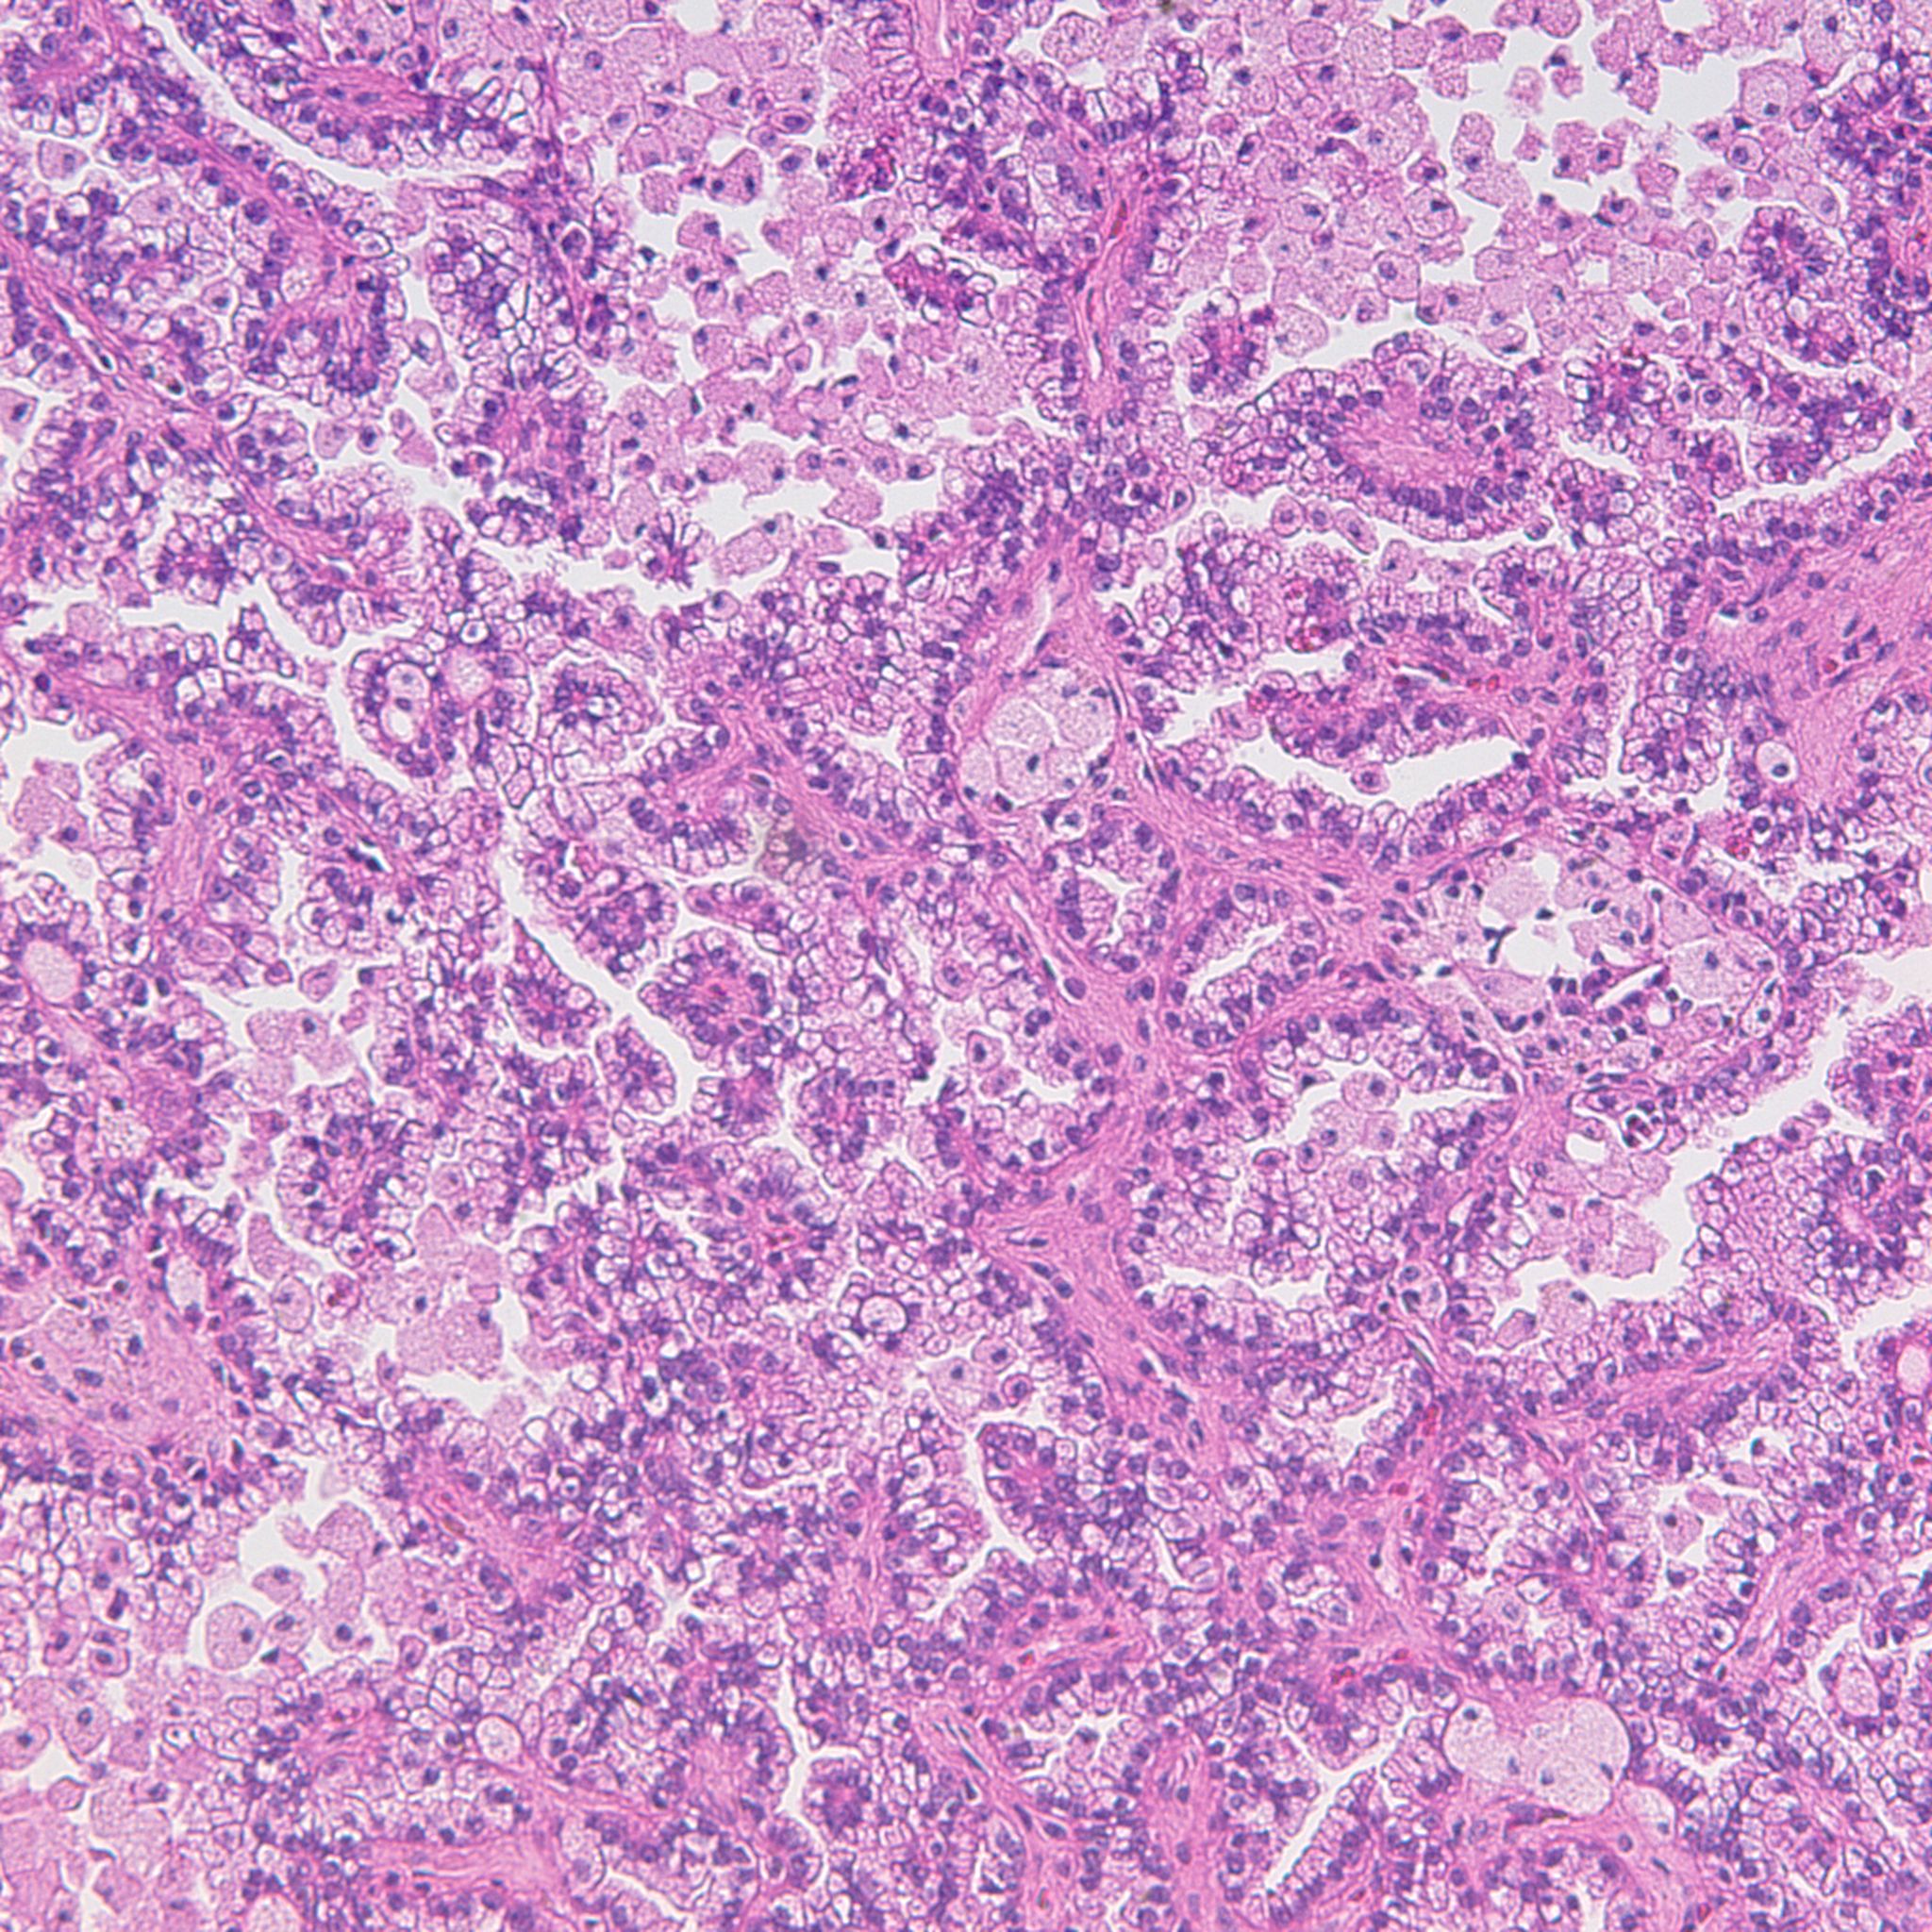

Case ID: 1225

Consensus grade: Papillary RCC (Type 1)

Case description (by case creator):

Papillary renal cell carcinoma, type 1, Fuhrman nuclear grade 2